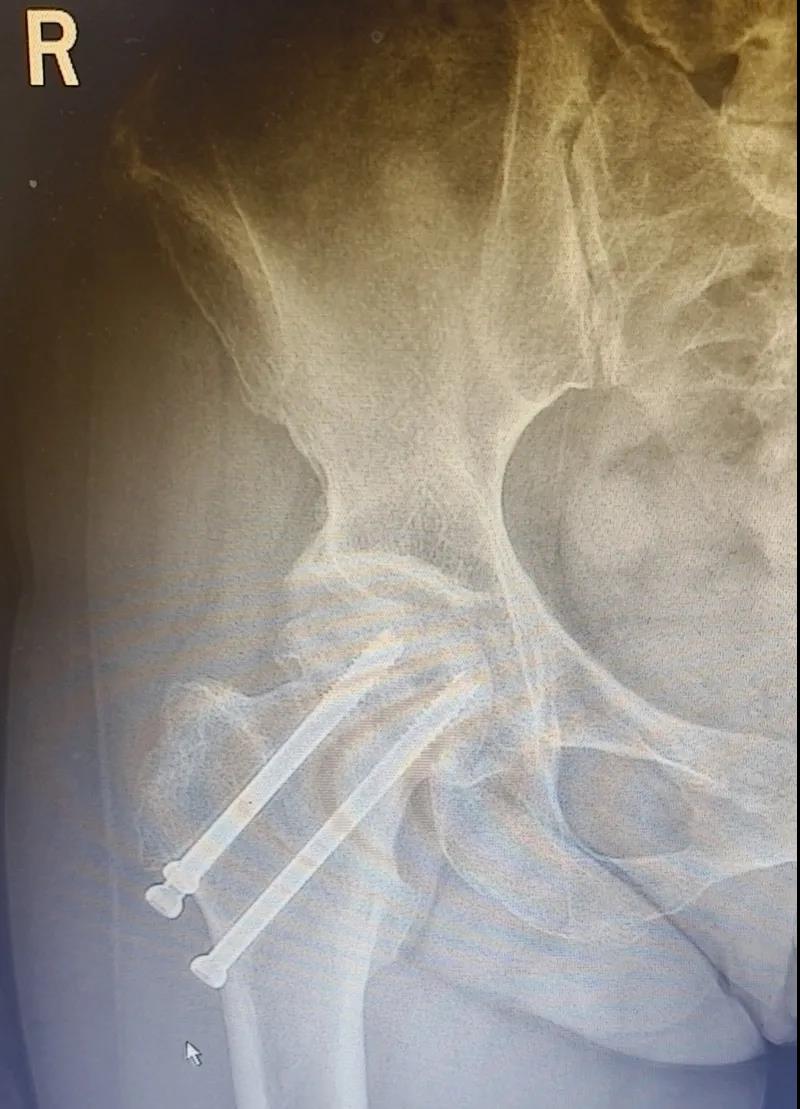

兩個(gè)月后,李女士的腿已與常人無(wú)異,苦纏2年有余的病痛,終于徹底消散。

(△做完“右股骨頸全髖關(guān)節(jié)置換術(shù)”后的影像)